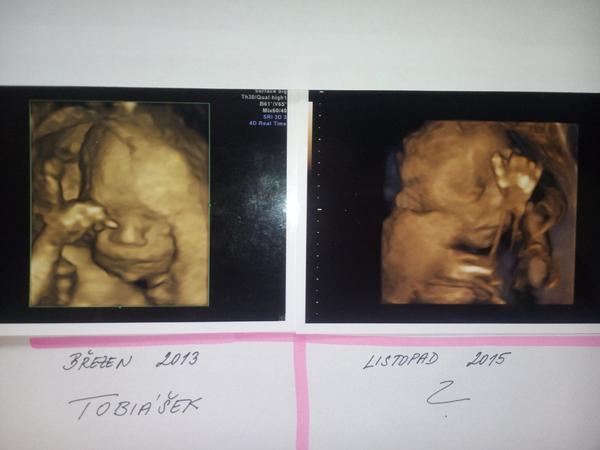

@janesafari mě teda přijde podle 3D ze je to holčička, ale nevím syn ležel v bříšku jinak tak má fotku jinou tak schválně dívej 🙂

@janesafari to vypadá jak dvojčátka 🙂 😉 jasný kluk to druhý 🙂

@maminkapetula to je holčička 😉 😉 má krásný jemný obličejík a ten krásný nosík...

@janesafari je fakt že u tebe z UTZ to jde krásně poznat. Jsou to jasný klučičí rysy. Taky mpůjdu na 3D ale musím se tam objednat, tak jsem zvědavá jak moc odlišný od malé bude... 🙂

@maminkapetula Taky bych tipovala holčičku 🙂

@janesafari my doufáme, že tam taky princezna v bříšku je , protože se stále nemá k tomu to odkrýt 😀 ☹ ale u Tebe teda vidím druhého krásného chlapečka u prvního bych to moc nepoznala